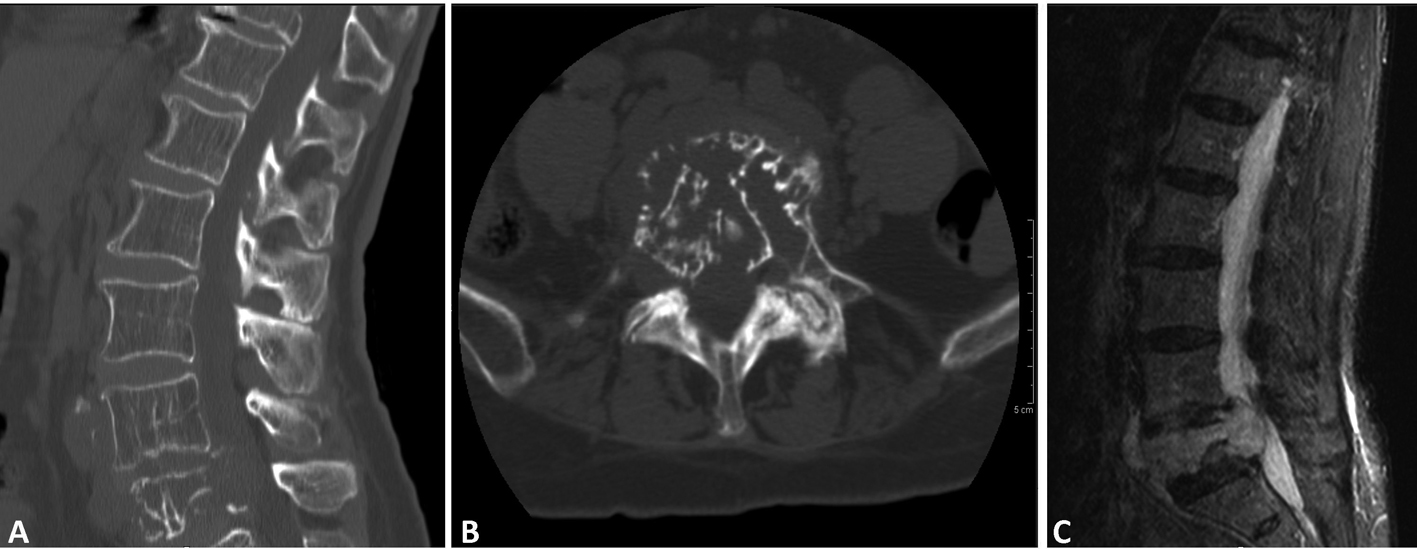

Computed tomography (CT) of the lumbar spine demonstrated a compression fracture at L5 with a soft tissue density mass causing significant canal stenosis at that level (Fig. 1A, B). An MRI scan obtained demonstrated an osteolytic lesion, compression fracture of L5, and a soft tissue mass with 1 cm retropulsion causing significant canal stenosis (Fig. 1C). AP and lateral radiographs of the T-spine showed degenerative lumbar scoliosis, and grade I L4 on L5 anterolisthesis. CT of the chest, abdomen and pelvis did not reveal evidence of neoplasm except the L5 lesion.

![]() Click for large image | Figure 1. (A); (B); (C) (CT - sagittal, axial and MR T2- sagittal) soft tissue lesion extending both anteriorly and posteriorly causing canal stenosis, and destructed vertebral body, with canal involvement. |